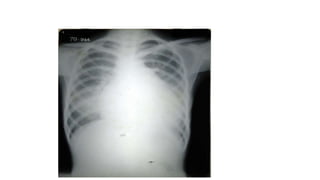

A normal chest x-ray shows the lungs, heart, bones, and soft tissues appearing healthy and unobstructed. The document discusses the different views used in chest x-rays, including PA, AP, lateral, and lateral decubitus views. It also covers topics like depth of inspiration, rotation exposure, the lobes of the lungs, identifying the heart, and how to read a normal chest x-ray.